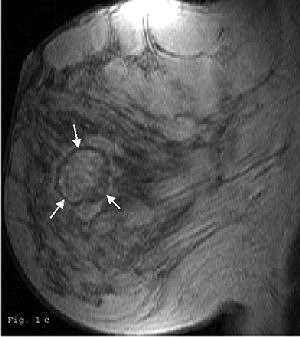

| Forty-five-year-old woman with 3-cm clinical lesion in lower quadrants of breast. Late postcontrast sagittal T1 fast spoiled gradient-echo image shows peripheral decrease of signal (arrows). |